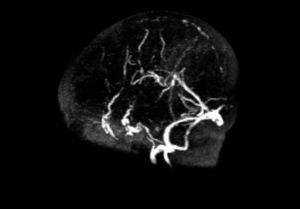

Se realizan las siguientes pruebas complementarias: radiografía de tórax donde se observa discreta cardiomegalia y signos de edema agudo de pulmón; ecografía abdominal (fig. 1) objetivándose un gran trombo que ocupa prácticamente toda la luz de la aorta abdominal desde la parte distal de la mesentérica superior hasta la bifurcación de ambas ilíacas. Ecografía transfontanelar: presencia de un trombo en el seno longitudinal superior, confirmado en la resonancia magnética (fig. 2) y en la angiografía cerebral (fig. 3) realizadas posteriormente.

Figura 1. Ecografía abdominal realizada a las 72 h del ingreso, donde se observa un gran trombo en la aorta abdominal.